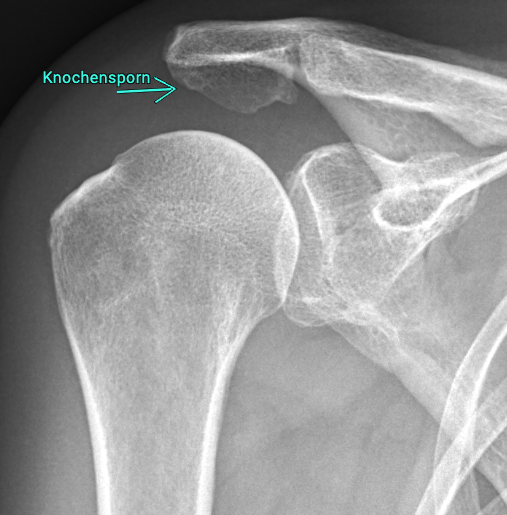

Das Engpasssyndrom, auch bekannt als Impingementsyndrom, zählt zu den häufigsten Ursachen für Schulterschmerzen. Dabei handelt es sich um eine mechanische Enge im Schultergelenk, bei der die Rotatorenmanschettensehnen und der Schleimbeutel zwischen Oberarmkopf und Schulterdach eingeklemmt werden. Oft ausgelöst durch eine Dysbalance oder mangelnder Zentrierung des Oberarmkopfes in der Gelenkpfanne, manchmal auch durch einen Knochensporn am Schulterdach

Diese Reibung führt zu Schmerzen, vor allem bei Überkopfbewegungen oder beim seitlichen Anheben des Arms.